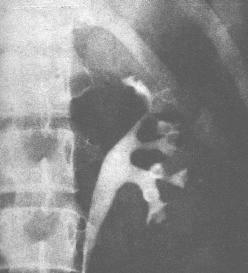

腎結核病理圖 診斷

腎結核病理圖 腎結核繼發於全身性結核病,因此在治療上必須重視全身治療並結合局部病變情況全面考慮,才能收到比較滿意的效果。